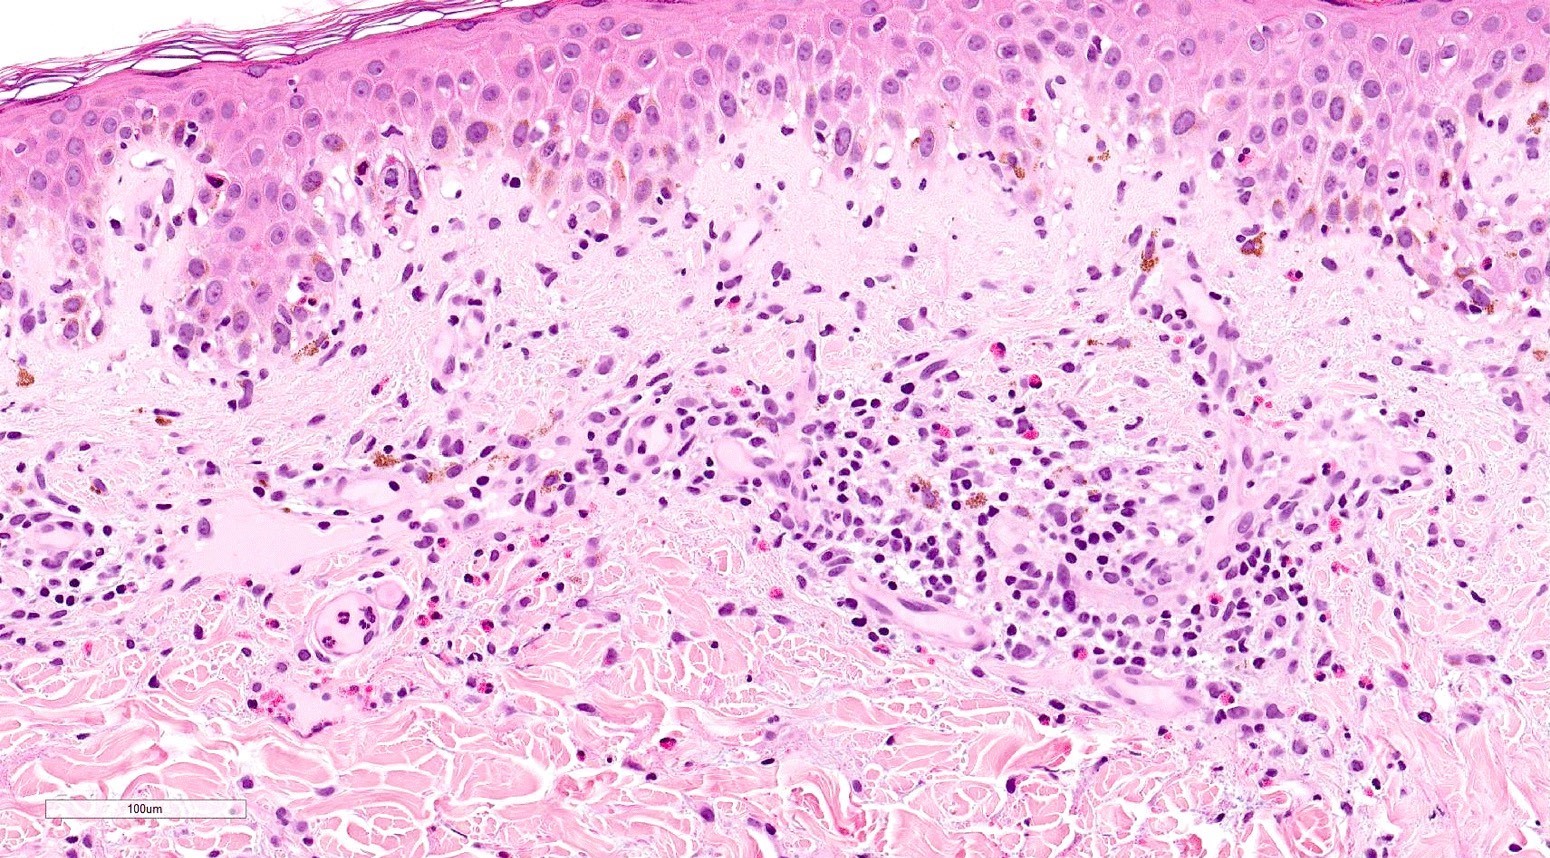

Microscopic (histologic) description

- Acute GVHD (Patterson: Weedon's Skin Pathology, 4th Edition, 2015)

- Mild to moderate superficial perivascular lymphocytic infiltrate with exocytosis of inflammatory cells into the epidermis and basal vacuolation, interface dermatitis

- Scattered, shrunken, eosinophilic keratinocytes with pyknotic nuclei, at all levels of the epidermis; often accompanied by 2 or more lymphocytes, producing the satellite cell necrosis - lymphocyte associated apoptosis

- Occasionally, rare eosinophils can be present; melanin incontinence is prominent in patients with darker skin types

- If severe, subepidermal microvesicles, subepidermal blisters and epidermal necrosis

- Lymphocytic infiltrate in GVHD after solid organ transplantation is usually brisk in comparison to the sparser inflammation following bone marrow transplantation

Microscopic (histologic) images

Contributed by Silvija P. Gottesman, M.D. and Ohoud Aljarbou, M.D.